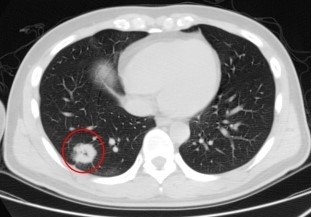

小刘肺上的“疑团”。通讯员张全录 蒋钰辉 摄

35岁的小刘年初发现右侧颈部鼓起一个包块,不痛不痒,触摸之下会来回活动,后来在武汉市肺科医院检查诊断为淋巴结结核病,需要手术治疗。不料,术前常规检查中,小刘又被发现肺上有一个“团块影”。医生按照常理推断,肺结核可能性大,然而术后小刘继续服用抗结核药物治疗肺上团块,却未见奏效。

随后,外科专家根据相关检查结果研判,一致认为肺癌可能性大。想要明确诊断,需要对小刘进行穿刺活检。听闻肺上可能有不好的结果,小刘心存恐惧,抱着“没有消息就是好消息”的心态,拒绝进一步检查。